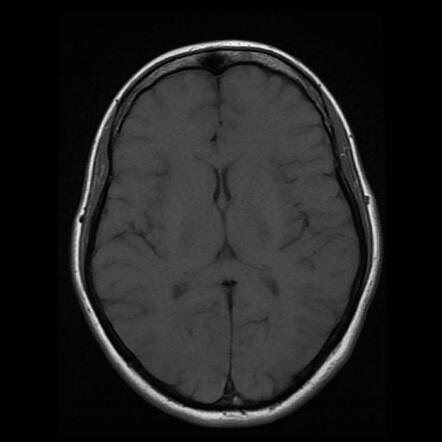

МРТ головного мозга: показания и результаты

Раздел: Визуальный дайджест